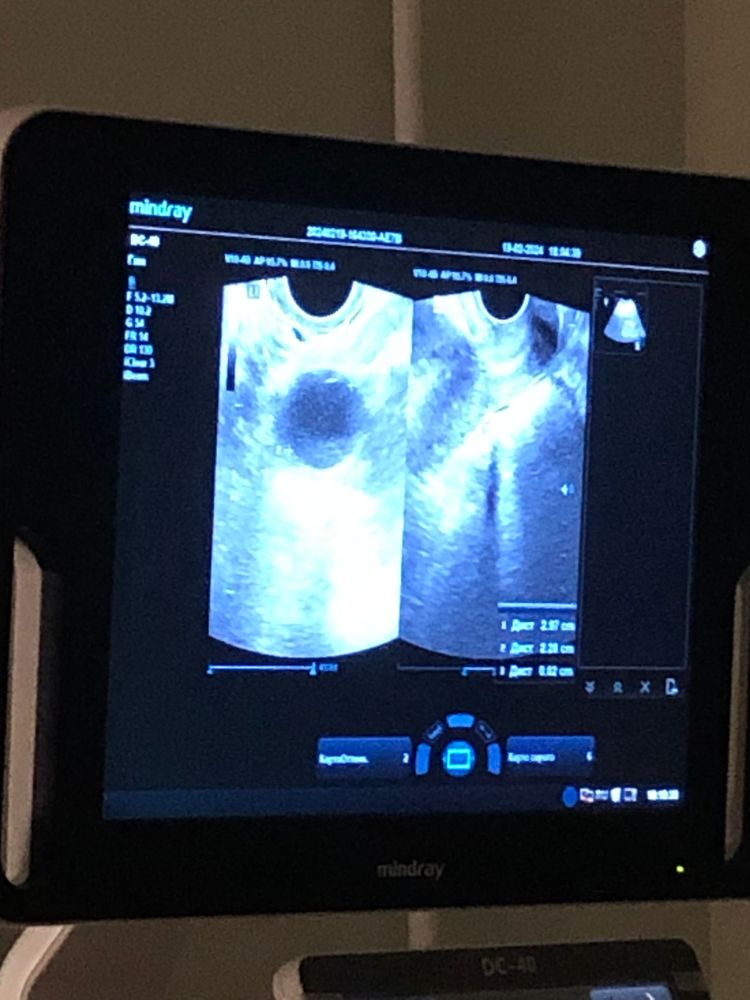

Девочки, вчера на узи доминантный фолликул был 25мм, сразу кололи хгч , сегодня сходила на фолликулометрию

нет ни доминантного,ни желтого тела ,ни жидкости

Кристина , так на фото же доминантный фолликул? Хорошо что я сфоткала

она очень долго смотрела ,так как яичник находится над маткой